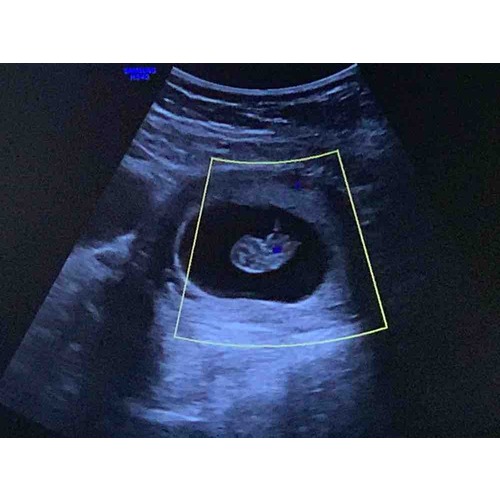

Inwendig! 7+4